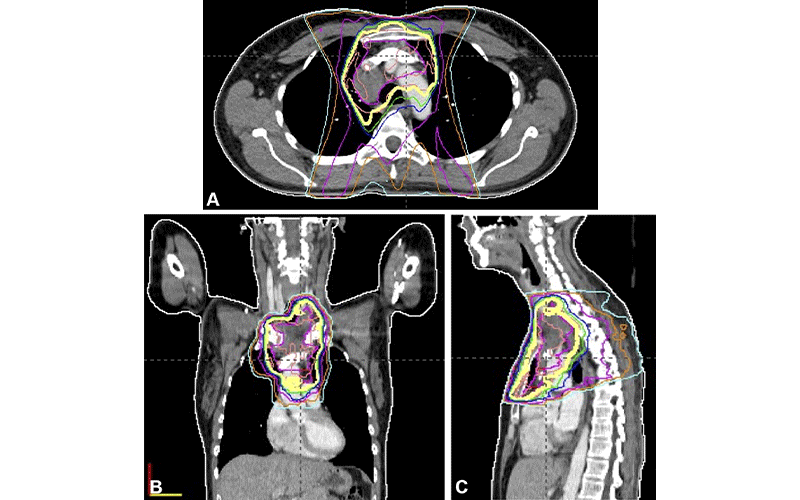

“Although the planning and delivery techniques of radiation therapy have evolved substantially during the past few decades, the structures surrounding the target lesion are inevitably exposed to radiation,” Dr. Katsura explained.

Radiologists should also maintain familiarity with the patient’s timeline and expected imaging appearances after radiation therapy. Knowledge about the radiation treatment plan, number of normal structures included, location of the target lesion and amount of time elapsed since radiation therapy are all particularly important at follow-up imaging.

“As treatment options in oncology continue to expand and long-term survival increases, diagnostic radiologists should be familiar with the patient’s timeline and expected imaging appearances after radiation therapy to avoid pitfalls in image interpretation,” Dr. Katsura concluded.